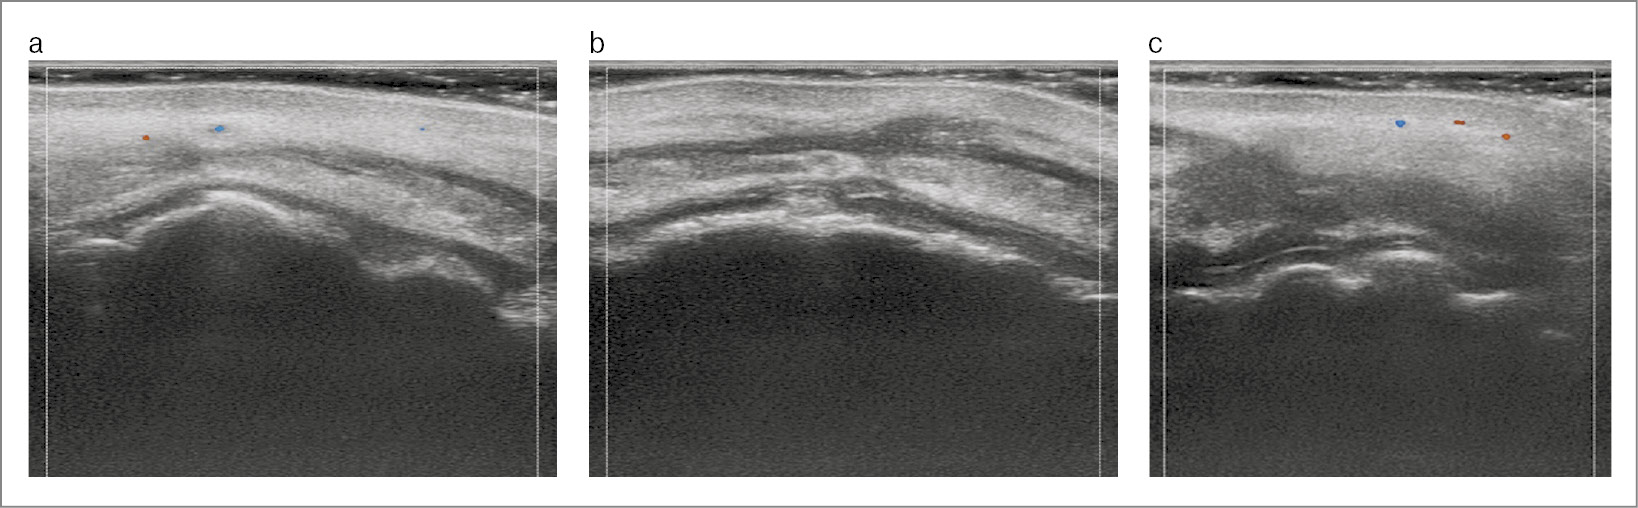

По данным УЗИ контрольного приема в кожной части верхней губы отмечено уменьшение объемов кожной части верхней губы, филлера и интерстициального отека (рис. 3, а). В проекции колонн фильтрума, где визуализируется восстановление структур в области колонн фильтрума, ткани хорошо дифференцированы, признаков внутрисосудистого компонента, гипоэхогенных образований (филлеров), инкапсулированных образований не определяется (рис. 3, b). В области слизистой верхней губы отмечались ультразвуковые признаки восстановления васкуляризации, ткани достаточно дифференцированы – слизистый и подслизистый слои, мышца визуализировалась отчетливо, фрагментов анэхогенных включений (филлер) не отмечено (рис. 3, c).

Рис. 3. УЗИ контрольного приема: а – кожная часть верхней губы; b – проекция колонн фильтрума; c – слизистая верхней губы.